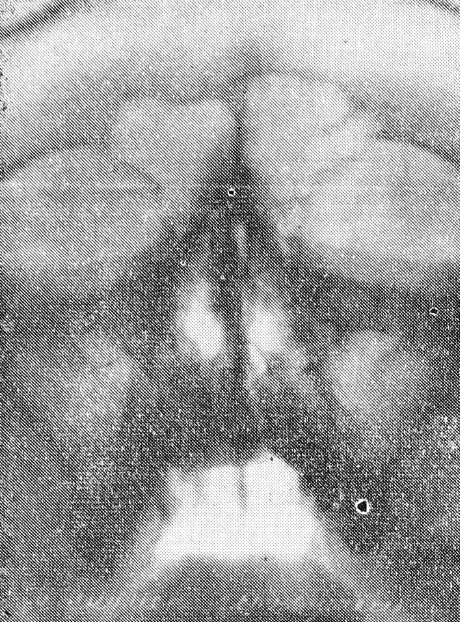

При помощи данного приспособления можно производить снимки придаточных пазух в вертикальном положении больного на аппаратах всех систем, внося при необходимости несущественные изменения. Мы производили снимки на аппарате УРДд-110-К4 при режиме: большой фокус, 67 кв, 50 МА, экспозиция 2,5 сек, фокусное расстояние 67 см (рис. 3, 4).

Рис. 4. Снимок того же больного в вертикальном положении. В обеих гайморовых пазухах отчетливо определяется горизонтальный уровень жидкости.